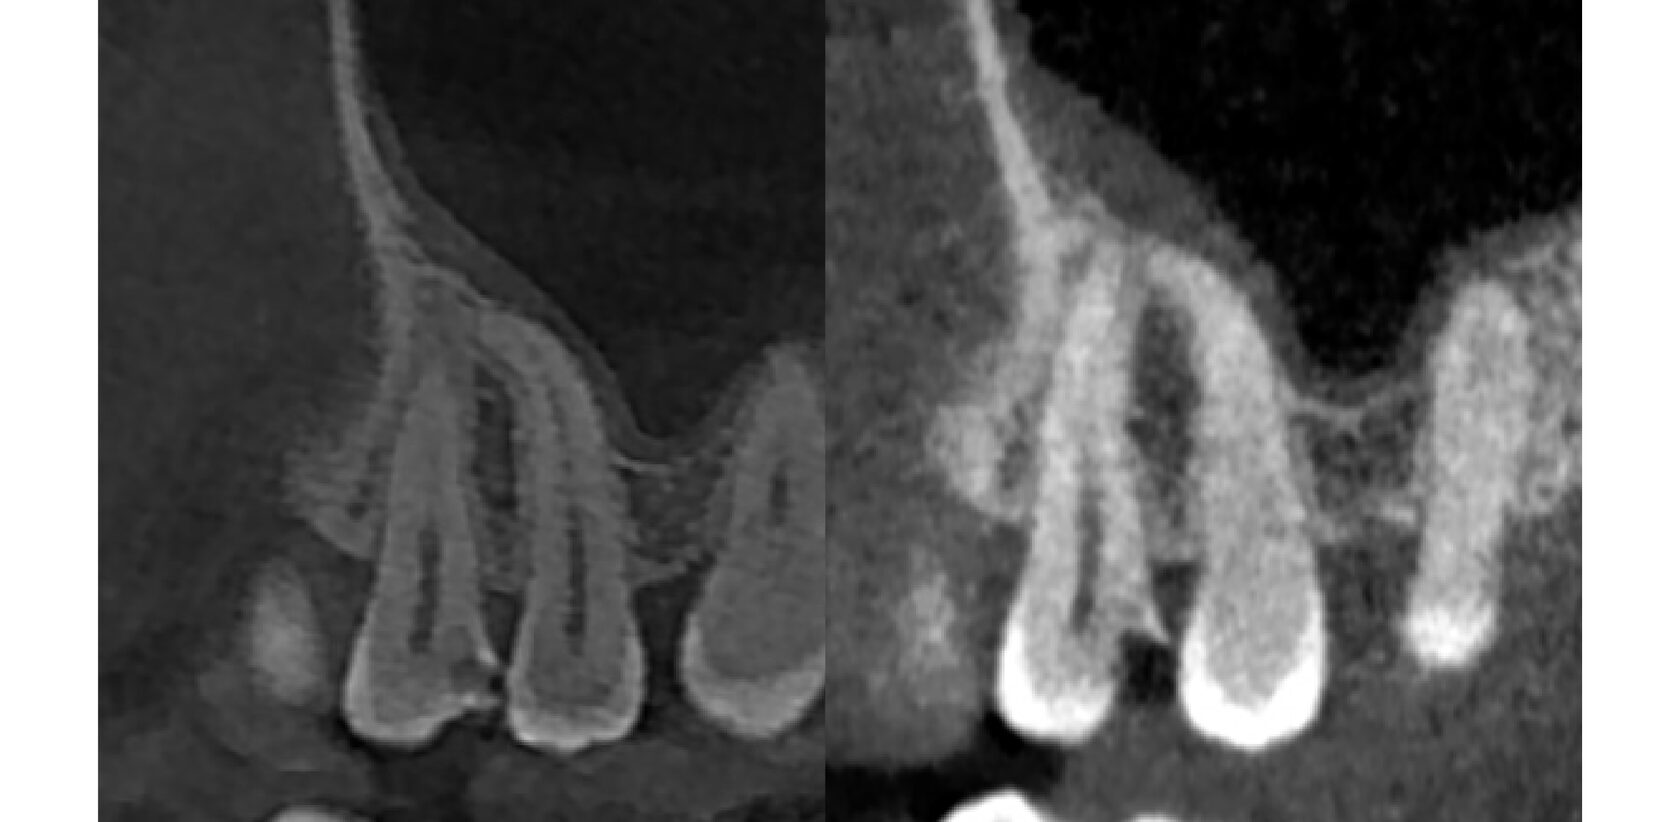

При осмотре и на снимке мы видим уже совсем другую картину. кариозная полость сильно углубилась и достигла нерва, поэтому зуб давал такую сильную боль.

Нами было проведено эндодонтическое лечение внутренностей зуба, предварительно восстановив сломанную стенку и изолировав зуб от слюны.

Эндодонтическое лечение проводилось согласно клинических рекомендаций ВОЗ и протоколов нашего центра. Корневые каналы промыты, избавлены от очага инфекции и плотно запломбированы, что подтверждается на контрольном снимке.